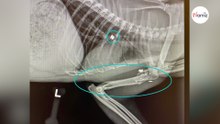

Rifugio salva un gatto gravemente ferito: le radiografie del veterinario rivelano l'impensabile